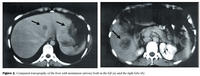

Magasondu var komið fyrir og sjúklingnum gefinn vökvi og sýklalyf í æð. Ristilspeglun daginn eftir sýndi þrengingu í efri hluta vinstri ristils og neðan við hann stóran ristilsepa. Einnig var fengin tölvusneiðmynd af kviði sem sýndi fyrirferð við áðurnefnda þrengingu auk tveggja þéttra fyrirferða hvora í sínu lifrarblaði (mynd 2).

Ný ristilspeglun reyndist eðlileg. Rúmum tveimur mánuðum eftir aðgerðina var hafin meðferð með frumueyðandi lyfjum, flúoróúracíli og levamísóli. Þeirri meðferð var haldið áfram í rúma sex mánuði og þoldist meðferðin vel. Lifrarpróf héldust eðlileg og CEA (carcinoembryonic antigen), sem var vægt hækkað fyrir aðgerð, varð eðlilegt eftir að meðferðin hófst. Hálfu ári eftir lifraraðgerðina hækkaði CEA að nýju. Nýjar sneiðmyndir af lifur sýndu merki eftir undangengið lifrarúrnám en að auki nýja fyrirferð neðarlega í hægra lifrarblaði (mynd 5). Önnur meinvörp greindust ekki í kviðar- eða brjóstholi og slagæðamyndataka af lifur gaf til kynna að hægt væri að komast að meinvarpinu með skurðaðgerð.